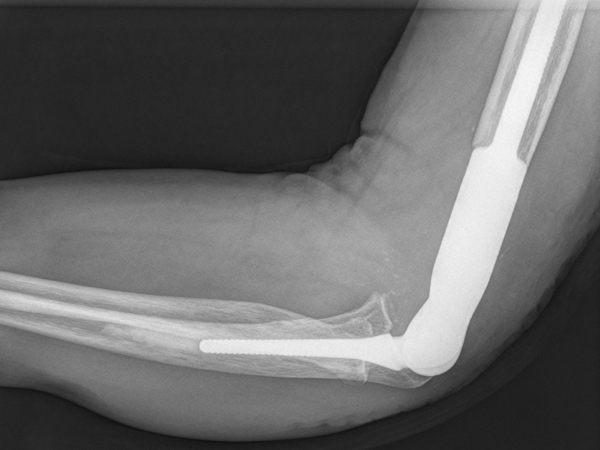

2014-01-07佛山首例人工肘關(guān)節(jié)置換手術(shù)在我院完成

近期,我院骨科成功為一名60歲的老伯進(jìn)行了人工肘關(guān)節(jié)置換,這是我院繼髖、膝、肩關(guān)節(jié)置換術(shù)后開展的又一項(xiàng)新技術(shù),也是佛山市首例成功的人工肘關(guān)節(jié)置換手術(shù)。 馮老伯日前因左肘關(guān)節(jié)疼痛、活...閱讀全文